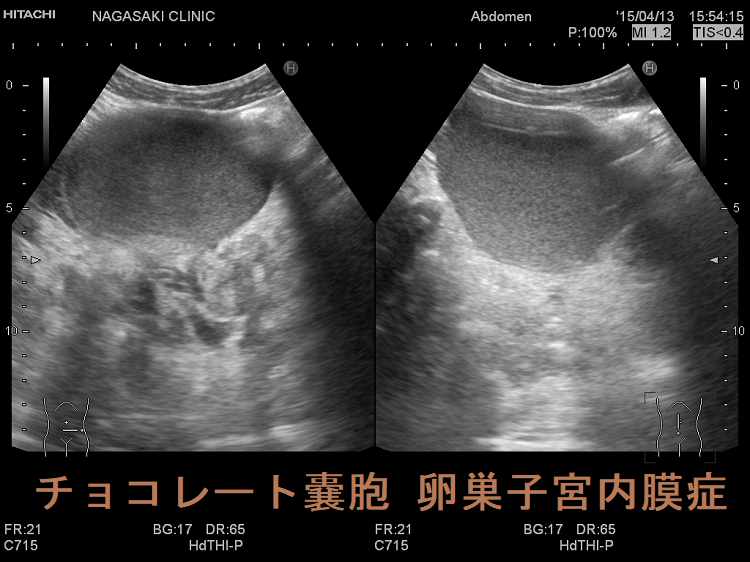

長年に渡る重度の甲状腺機能低下症により、粘液多糖類(ヒアルロン酸、コンドロイチン硫酸塩)沈着と卵胞発育異常が生じ、卵巣容積増加・卵巣嚢胞(卵巣嚢腫)形成促進。卵巣茎捻転の危険。甲状腺ホルモン補充療法により甲状腺機能正常化すると、遅れて卵巣容積・卵巣嚢胞減少。チョコレートのう胞(卵巣子宮内膜症)は生理周期に合わせて子宮内膜剥離出血し、生理痛・不妊症・破裂して急性腹症。甲状腺乳頭癌術後のDWIBSで偶然発見される。過剰なエストロゲン刺激に関連する甲状腺疾患などが危険因子となり、約1%が子宮内膜症関連卵巣癌(EAOC)に悪性転換。

長年に渡る重度の甲状腺機能低下症により、卵巣容積は増加し、卵巣嚢胞形成が促進されます。

チョコレートのう胞(卵巣子宮内膜症、ovarian chocolate cyst)は、子宮内膜が本来存在しないはずの卵巣に発生する子宮内膜症の一種です。 20~30代前半に好発し、生理周期に合わせて子宮内膜が剥離し出血をおこします。それが卵巣内にチョコレートの様な状態で蓄積し、チョコレートのう胞(チョコレート嚢胞)を形成します。

骨盤部単純MRI 画像では、背側が低信号になる(shading)。